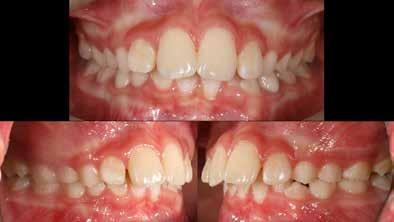

Lány páciensem I. fázisú kezelését 10 évesen kezdtük el bimaxilláris funkciós, kivehető készülékkel. Megfigyelhetőek a class 2-es eltérésnél tipikusan jellemző szűk felső és alsó fo-

gívek, valamint a nagy overjet, a mandibula disztál helyzete, továbbá a felső metszőfogak protrúziója, amelynek kialakulásához sokszor hozzájárul az ujjszopás is (1-3. képek)

A vegyes fogazati kezelési célok a fogívek tágítása és a mandibula meziális irányú növekedésének a biztosítása volt. Fontos, hogy az ilyen típusú készülékeket nem csak éjszaka, hanem napközben is – amennyit csak lehet – hordani kell a minél hatékonyabb működés érdekében. A 18 hónapos első fázisú kezelésnek köszönhetően az alap kezelési célok megvalósultak, sikerült a class 1-es okklúziót beállítani (4-7. képek).